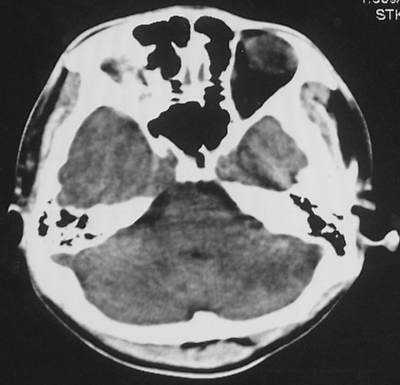

患者、男、18y,头痛5天入院。

左小脑、右丘脑区低密度影,无明显强化及占位表现,男18y,先考虑脑部炎性病变,如脑炎、血行播散性感染等,建议结合临床如脑脊液检验。

单独看左侧小脑半球的不规则形囊性低密度灶,从发病部位、年龄以及无强化、无占位效应的特点可以考虑毛细胞瘤型星形细胞瘤。同样,如果单独看右侧丘脑的近圆形低密度,也可以考虑囊变形星形细胞瘤。只是胶质细胞瘤一般为单发直接浸润、蔓延生长,而不是在脑内同时出现多个病灶,且瘤周没有一点儿水肿,暂时不予以考虑。

同时,现在已经进入冬天,一氧化碳中毒也需要考虑进去。不知道增强是什么时间做的,与平扫间隔几天?如果中间时间比较久而且进行吸氧等治疗,则平扫所示右侧颞叶密度比较低、右侧小脑半球以及脑桥也似有片囊状低密度,但在增强却没有发现就可以比较合理的解释了。